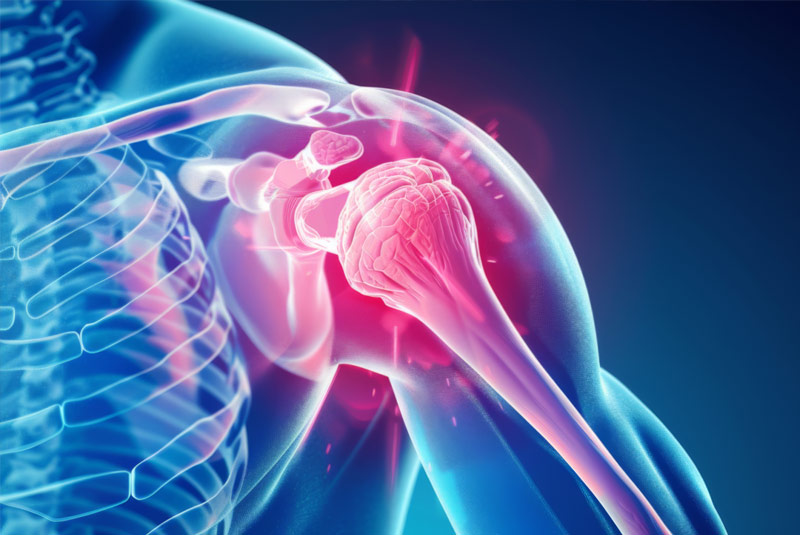

Έχει 5ετή μετεκπαίδευση και εργασία στο Ηνωμένο Βασίλειο ως ειδικός Ορθοπαιδικός Χειρουργός. Έχει εργαστεί στα Ορθοπαιδικά Τμήματα των Νοσοκομείων Southampton University Hospitals NHS Trust, Leeds Teaching Hospitals NHS Trust και στο Northampton General Hospital NHS Trust, με υποεξειδίκευση στη Χειρουργική Ώμου, Γόνατος, Ισχίου, Ποδοκνημικής & Άκρου Ποδός, Ώμου & Αγκώνος και Γενικού Τραύματος Ενηλίκων και Παίδων.

Κατά τη διάρκεια της εργασίας του στο Ηνωμένο Βασίλειο εκπαιδεύτηκε σε σύγχρονες τεχνικές Αρθροσκοπικής Χειρουργικής και Επανορθωτικής Χειρουργικής Ισχίου, Γόνατος και Ώμου. Επιπλέον έχει δώσει πολυάριθμες διαλέξεις και έχει εκπαιδεύσει νεότερους Ορθοπαιδικούς και φοιτητές Ιατρικής. Αξιοσημείωτο και πλούσιο είναι το επιστημονικό του έργο με συμμετοχή σε δεκάδες συνέδρια και σεμινάρια στην Ελλάδα και στο εξωτερικό και έχει πληθώρα προφορικών ανακοινώσεων και δημοσιεύσεων.